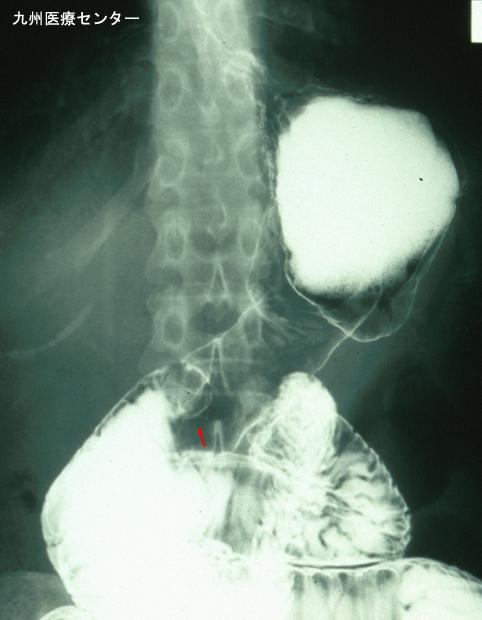

疾病(病理主体)的分类恶性上皮性肿瘤/腺癌

部位(按器官分)十二指肠/下行脚

检查方法X线

肿瘤的肉眼分类0型(表在型)/I型(Ip)

肿瘤最大直径25~29

肿瘤的深度sm